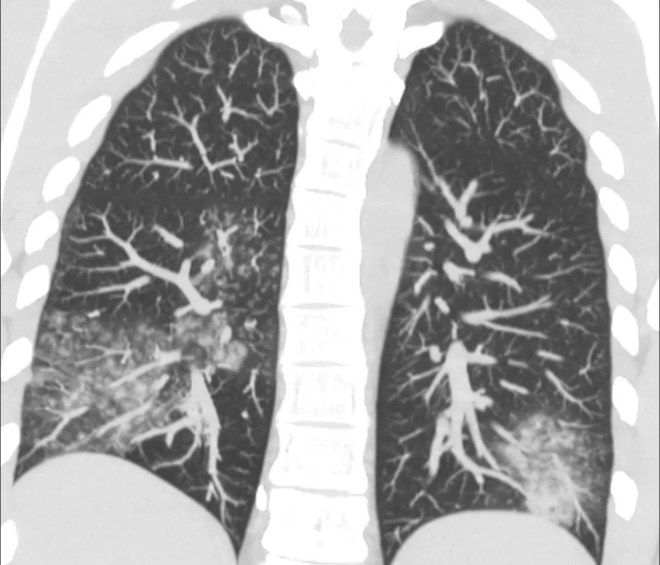

«Рентгенологические изменения неспецифичны: «матовое стекло», ателектазы, гиперраздутые лёгкие, иногда – консолидация. Чаще двусторонние поражения (смотрите фото)», — информирует инфекционист.